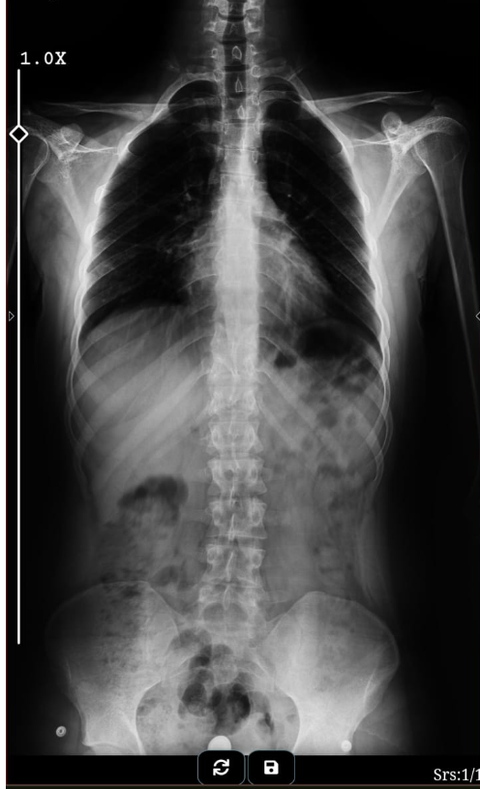

Skolyozum kaç derece gibi duruyor